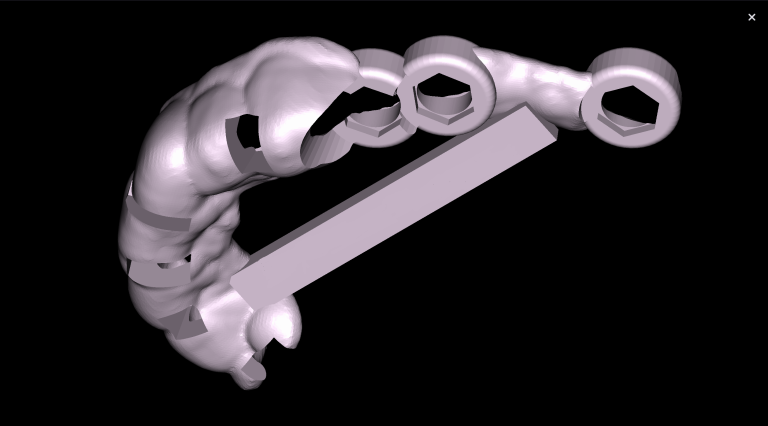

The “Third Molar Report” is a tool created by Diagnocat AI, it creates an optimal 3D visualization which helps to assess the position of the roots of the third molars relative to the roots of adjacent teeth and the floor of the maxillary sinus.